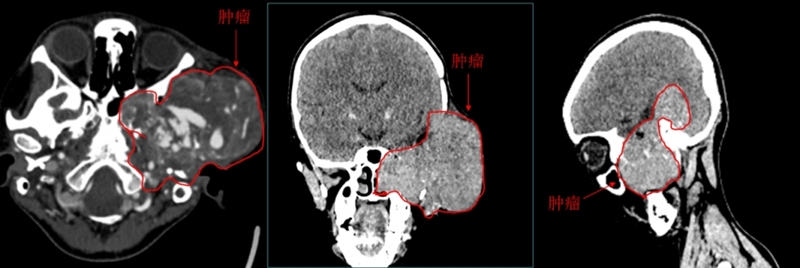

小辉被收治入院,但经过相关检查发现,情况比想象中还要复杂和困难。神经外科学科带头人程远教授阅片后指出:肿瘤已经长到了视神经管后方,毗邻海绵窦,肿瘤还突进了翼腭窝、鼻腔内,向后也毗邻了咽后壁,岩骨、乳突、颞部骨质均被肿瘤侵蚀,颞下颌关节受到了破坏……患者肿瘤颅内外沟通,体积大、位置深,手术治疗难度高、风险大。

为了尽快给出治疗方案,神经外科主任谢宗义教授立即组织科室进行大讨论。肿瘤巨大,累及重要的解剖结构,而且血供丰富,瘤体内大血管穿行,这意味着手术可能出血多。但对于神经外科擅长血管治疗专业组而言,他们也有应对方法,可以在术前先行造影,明确肿瘤的供血动脉,在情况允许下予以介入栓塞,减少术中出血,然后再切除颅内外肿瘤。